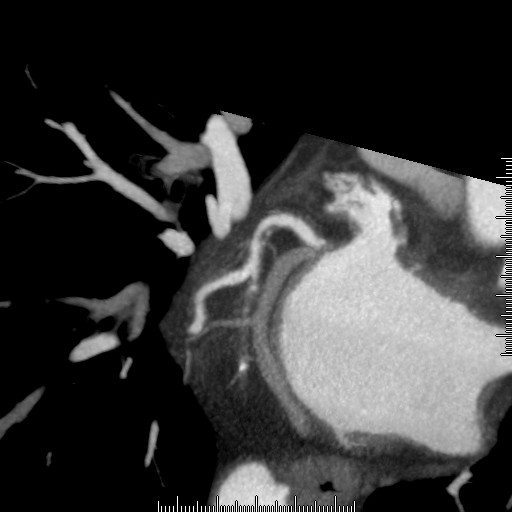

造影検査画像ビュー

画像は慢性完全閉塞症例。

造影検査では見えないプラークの分布もCTでは確認することできます。(白い部分が造影剤)

ステントが植え込まれた部分をアップにして形状評価も可能です